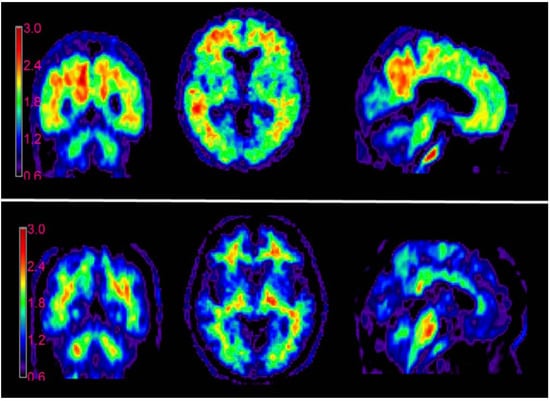

- Zhang, X.; Tian, Y.; Zhang, C.; Tian, X.; Ross, A.W.; Moir, R.D.; Sun, H.; Tanzi, R.E.; Moore, A.; Ran, C. Near-Infrared Fluorescence Molecular Imaging of Amyloid Beta Species and Monitoring Therapy in Animal Models of Alzheimer’s Disease. Proc. Natl. Acad. Sci. USA 2015, 112, 9734–9739. [Google Scholar] [CrossRef] [PubMed]